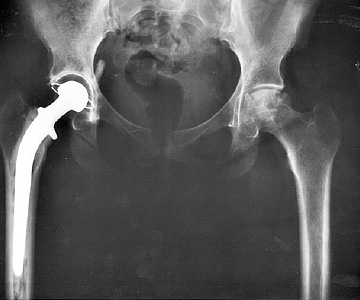

Hip joint replacement is the most common orthopedic joint surgery [1]. In the EU it is the second most common surgical procedure after Caesarean sections [2]. Rates for total hip arthroplasty (THA) are growing around the world and younger patients are undergoing the procedure; the American Academy of Orthopedic Surgeons (AAOS) reported a 123 percent increase between 2000 and 2009 in the 45 to 64 age group. While women are more likely to be recipients of an artificial hip, it has been estimated that more than 2.5 million Americans are living with this implant [3], with a further 300,000 Americans and more than 80,000 people in the UK receiving new hips each year [4].

Considering the frequency with which THA is performed, any tool that can assist surgeons with their tasks in the operating room, whether it be for primary or revision surgery, are usually welcome additions. Introduced in the 1980s and 1990s, modular implants were thought to help surgeons customize biomechanics. Modular implant pieces facilitated an easier achievement of offset, limb length, and anteversion, which is a complex endeavor [5].

The introduction of modular metal-on-metal total hip joint articulations with large heads (MoM THA) was seen as an opportunity and promoted by most device companies, embraced by many surgeons and as a result, a significant number of patients received this combination. Modular MoM THA appeared to be a great solution to stability issues, and an alternative to resurfacing, particularly for revisions due to failed femoral neck fracture [6].

It’s been asserted that surgeons only contemplate the strength of a material when choosing a modular junction. But this single consideration neglects a “totality of factors”, such as corrosion resistance, cost, and manufacturing constraints [7]. When it comes to selecting a femoral head, cobalt/chromium (Co/Cr) alloys are low cost and also strong, which are desirable features [8]. Coupled with the advantages of modular design (intraoperative flexibility, simplified procedures, decreased inventory) it is easy to see why modular metal implants are handy in the toolbox.

However, corrosion at the taper junction in modular hip implants is increasingly suspected to contribute to mortality, adverse tissue reaction, such as pseudotumors, and device failure [7, 8, 9, 10], regardless of the type of articulating bearing surface used [11]. One recalled modular head-neck stem implant has had reported failure rates of 86 percent within three to five years [12].